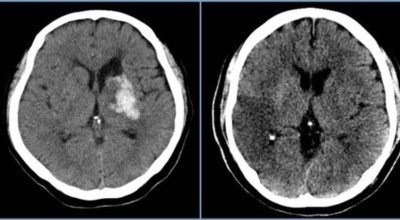

뇌출혈은 발작 직후 안정을 취해야 해요. 뇌부기를 가라앉히기 위해 약물 요법으로 고농도 포도당, 덱사메타존, 만니톨 등을 투약할 수 있고 뇌의 혈액 순환을 회복시키는 주사와 지혈제, 진정제 등을 활용할 수 있답니다. 혈종의 크기가 중등도 이상으로 마비 증세가 있다면 머리뼈에 작은 구멍을 내서 관을 넣어 혈종을 뽑아내는 수술을 시행할 수 있습니다.

혈압성 뇌출혈인 경우 혈종의 크기가 작으며 환자의 증상이 경미하면 약물 치료를 시행해요. 혈종의 크기가 아주 크며 뇌가 심하게 부어오를 때는 응급으로 머리뼈를 절개해 혈종을 빠르게 제거해야해요. 응급조치가 늦어지면 뇌압이 상승해 의식을 잃고 사망에 이를 수 있기 때문인데요 이렇게 증상이 심할 때는 수술이 잘 되었더라도 예후가 좋지 못할 때가 많다고 해요.